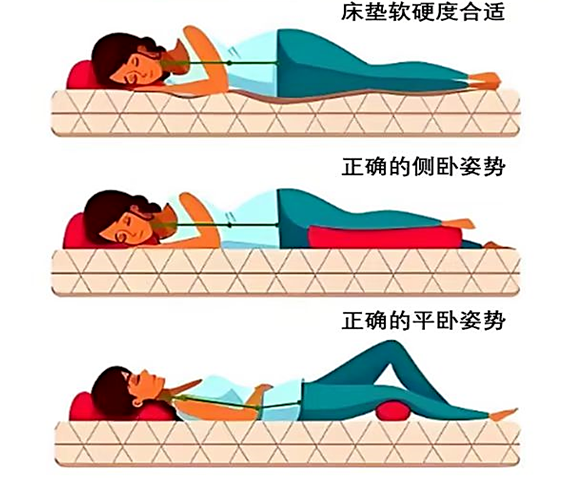

4.睡眠选对床和姿势:建议睡硬板床,能维持脊柱自然生理曲度;侧卧时可以在两腿之间夹一个枕头,让脊柱保持平直。